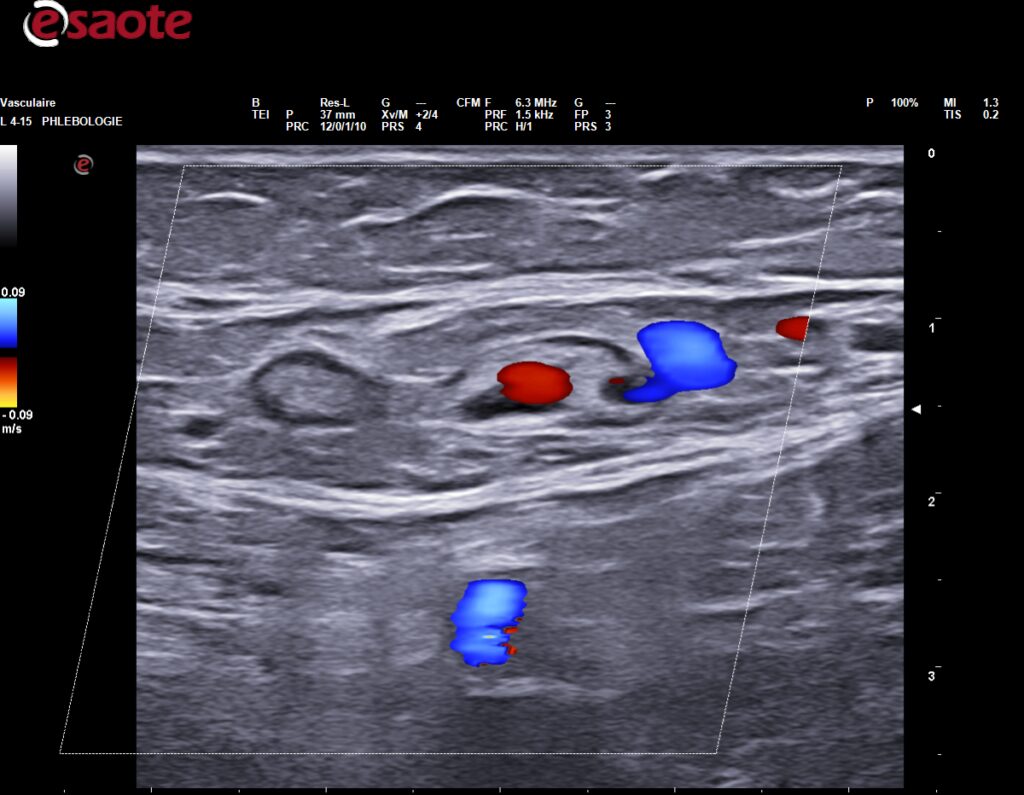

Nous publions ici la lettre ouverte du Dr Mario SICA Télécharger l’Article “ l’écho-sclérothérapie par mousse, une technique universelle sans universalité de soutien” Phlébologie annales vasculaires – 2008 – N°1 – 125-127